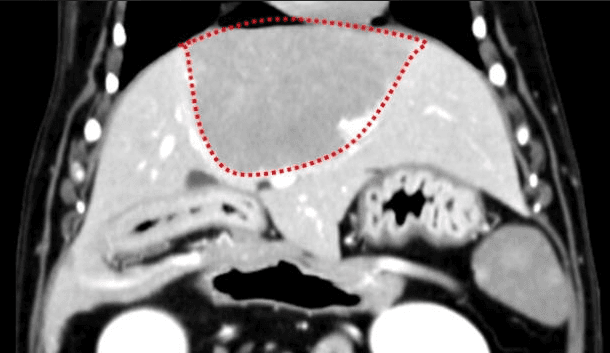

간, 담도 수술은 수술뿐만 아니라, 수술 후 중환자 관리도 중요하기 때문에 외과와 내과의 협진이 매우 중요합니다. 동탄시티동물의료센터에서는 최신 수술 장비의 도입으로 간담도 수술에서 출혈 및 부작용을 최소화 하였으며, 수술 후 협진 시스템을 통해 수술 후 관리에도 최선을 다하고 있습니다.

간종양

담석

담낭점액종